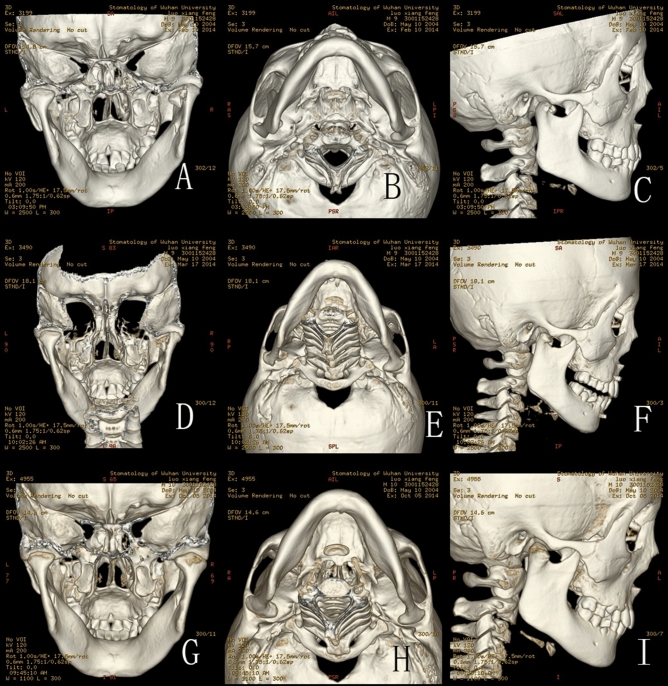

(A–C) CT scan in February 10th 2014 of a 9 year-old boy: (A) Back view of the fractures: CT scan showing right intracapsular fractures; (B) Bottom view of the fracture; (C) Lateral view of the right condyle; (D–F) CT scan in March 17th 2014: (D) Back view of the fracture: CT scan showing fracture fragment fused with ramus stump at the displaced position; (E) Bottom view of the fracture; (F) Lateral view of the right condyle: the lateral head of the condyle began to show signs of absorption; (G–I) CT scan in October 5th 2014: (G) Back view of the fractures: CT scan showing the remoulded condylar heads appeared smooth; (H) Bottom view of the fracture; (I) Lateral view of the right condyle: the lateral head of the condyle resorbed obviously.